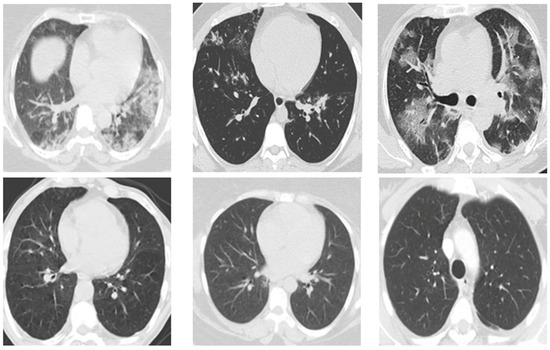

The suggested dataset (SARS-CoV-2) contains 2481 CT images shared among 1252 patients infected with COVID-19; and 1229 CT scans for non-COVID-19 patients that have other pulmonary diseases. Data were gathered from hospitals in Sao Paulo, Brazil. In this case, the data consist of 60 patients infected with coronavirus; 28 of them were female, and 32 were male [42]. The size of the images in this database was different; the size of all the images equalized before the pre-processing stage (Figure 2). The dimensions of the images vary; for example, the smallest size recorded in the database is 104 × 153, while the largest size is 484 × 416. Figure 3 displays several instances of CT scans from both SARS-CoV-2-infected and non-infected patients, which form part of the dataset.

Figure 3. Showcases a selection of CT scans included in the dataset, demonstrating examples of both SARS-CoV-2-infected and non-infected patients.

Fractalfract 08 00237 g003